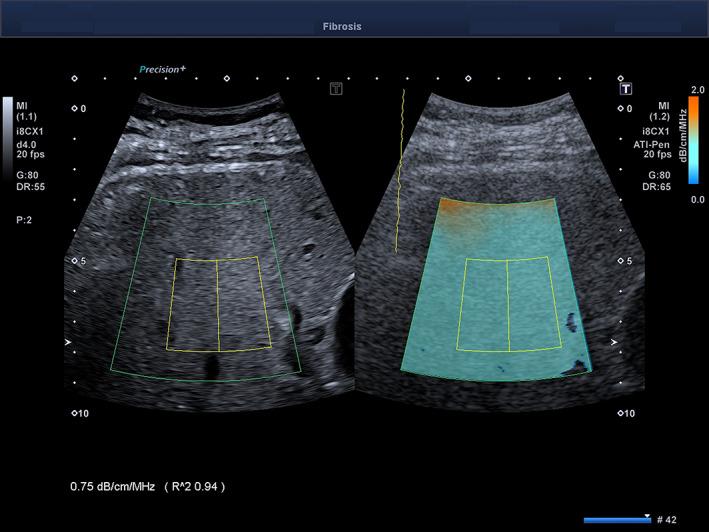

The main aim was to assess the performance and cutoff value for the detection of liver steatosis (grade S > 0) with the Attenuation Imaging-Penetration (ATI-Pen) algorithm available on the Aplio i-series ultrasound systems (Canon Medical Systems, Otawara, Japan). The magnetic resonance imaging-derived proton density fat fraction (MRI-PDFF) was used as the reference standard. Secondary aims were to compare the results to those obtained with the previous ATI algorithm (Attenuation Imaging-General [ATI-Gen]) and with the controlled attenuation parameter (CAP) and to generate a regression equation between ATI-Pen and ATI-Gen values.

Seventy-two individuals (31 male and 41 female) were enrolled. Correlation coefficients of ATI-Pen, ATI-Gen, and the CAP with the MRI-PDFF were 0.78, 0.83, and 0.58, respectively. The AUROCs of ATI-Pen, ATI-Gen, and the CAP for detecting steatosis (S > 0) were 0.90 (95% confidence interval, 0.81-0.96), 0.92 (0.82-0.98), and 0.85 (0.74-0.92), and the cutoffs were greater than 0.69 dB/cm/MHz, greater than 0.62 dB/cm/MHz, and greater than 273 dB/m. The regression equation between ATI-Pen and ATI-Gen was ATI-Pen = 0.88 ATI-Gen + 0.13.

Attenuation Imaging is a reliable tool for detecting liver steatosis, showing an excellent correlation with the MRI-PDFF and high performance with AUROCs of 0.90 or higher.